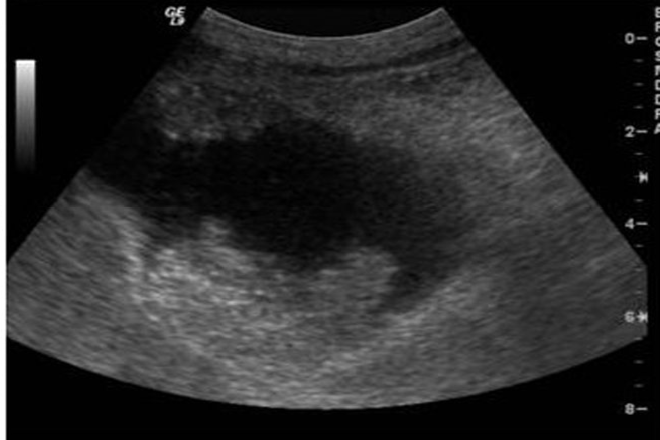

Diagnóstico por imagen de la vesícula en porcelana

En el estudio de los pacientes, la radiografía simple de abdomen y el ultrasonido resultaron ser herramientas útiles. De los pacientes estudiados, el ultrasonido fue el método más empleado (47%), seguido de la tomografía computarizada (16%). Algunos pacientes (37%) requirieron ambos estudios de manera complementaria.